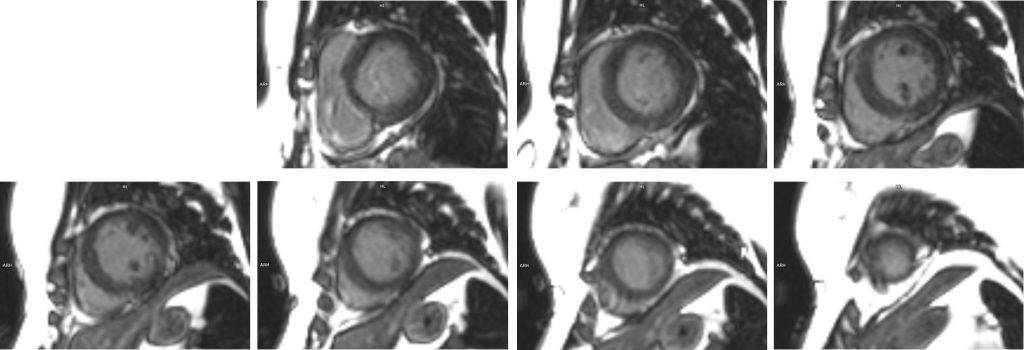

Examinarea IRM evidențiază formă tipică a ventriculului stâng care e balonizat, cu edem miocardic de la nivelul cavitații medii până la apex (examinarea cardiacă prin rezonanță magnetică este singura modalitate de a evidenția „in vivo” edemul miocardic) și, în mod caracteristic, fără priză de contrast ceea ce sugerează lipsa ariilor de necroză miocardică.

Cardiomiopatia de stress este un sindrom coronarian acut care, de cele mai multe ori, se vindecă fără sechele; examinarea cardiacă prin rezonanță magnetică este singura modalitate de a evidenția „in vivo” edemul miocardic şi, în plus, în acest caz este utilă deoarece evidențiază lipsa necrozei miocardice.